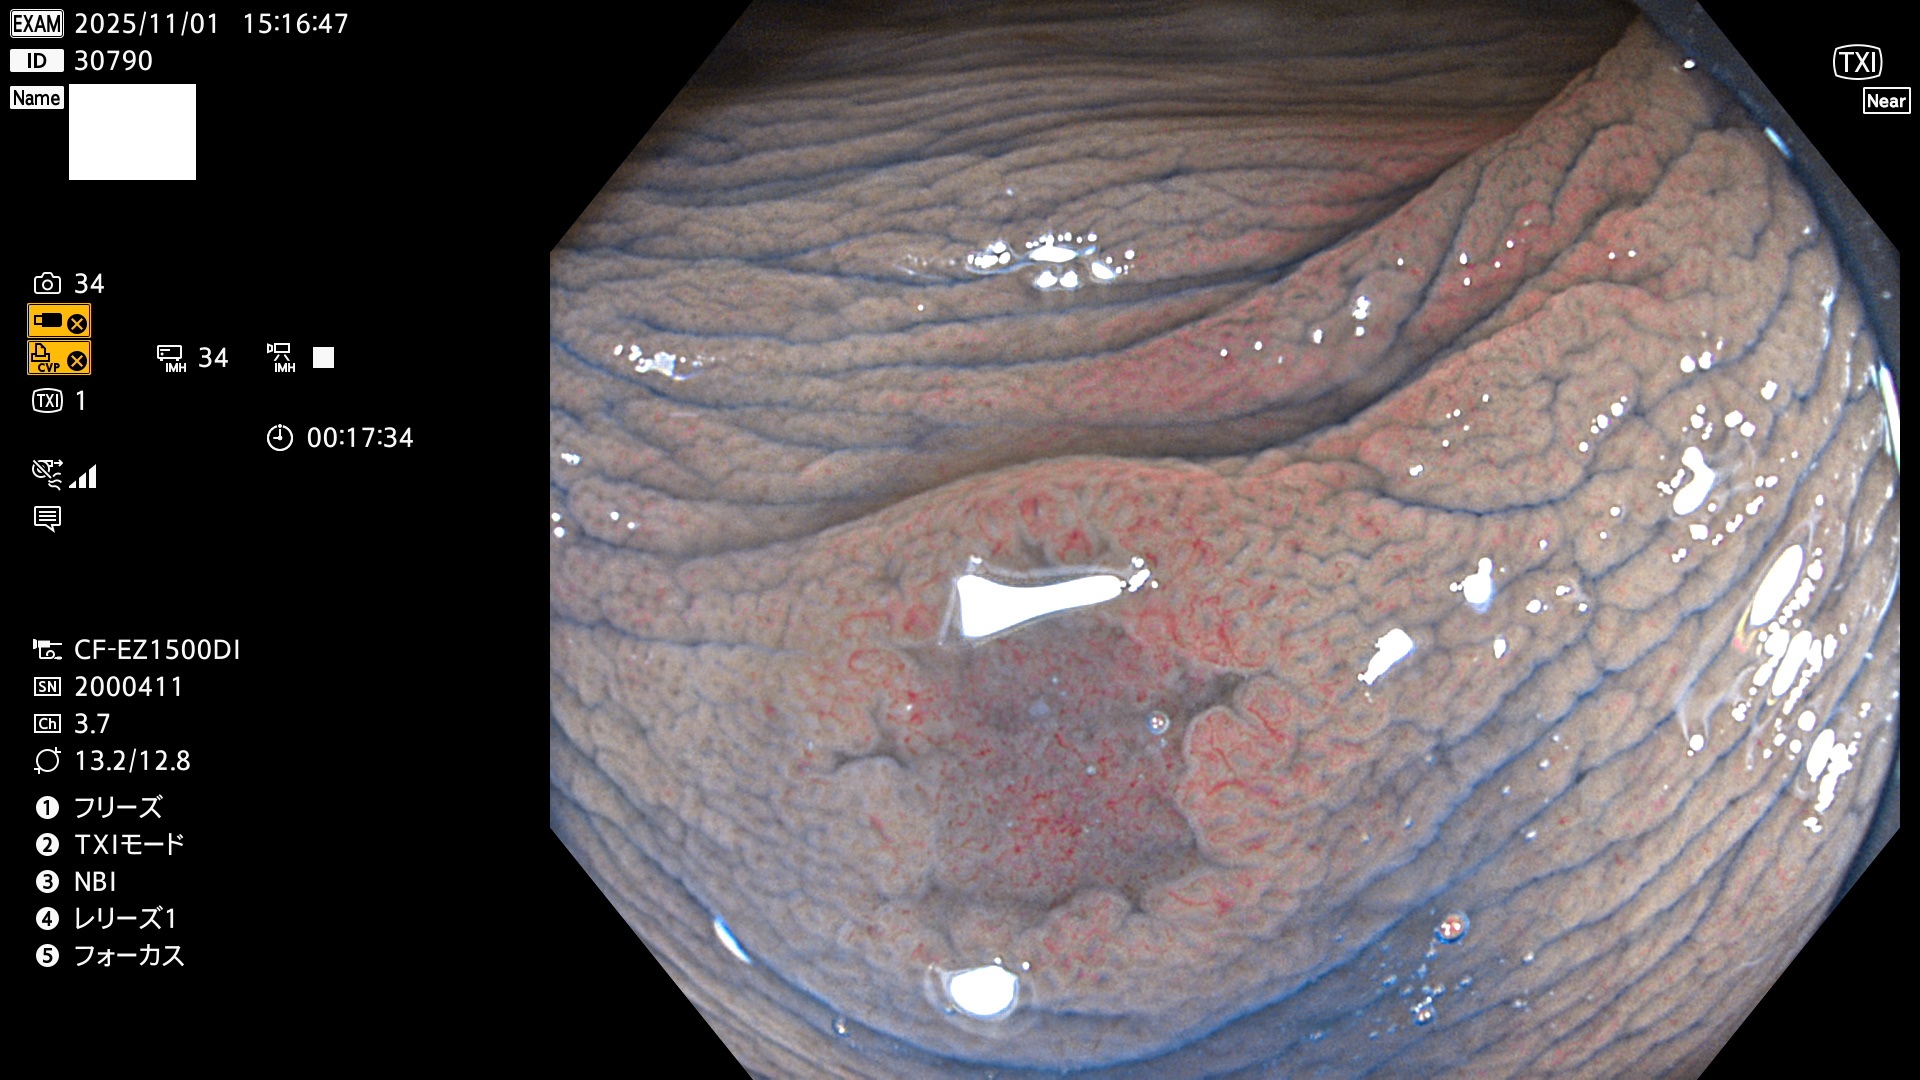

完全に平坦な物をUb、陥凹している物をUcと呼びます。Ubは認識が困難で、Ucはびらん(炎症)と紛らわしいために見落とされやすく、「内視鏡後・大腸癌」の原因になります。

専門的)Uc=De Novo癌? 内視鏡の解像度が低かった時代、このような説もありました。しかし今日の高精度内視鏡では良性の微小なUc型腺腫(APC遺伝子異常の腺腫)が日常的に見つかります。Ucこそが多段階発癌(Adenoma-Carcinoma Sequence)のMain Routeです。

毎週の検査(木・金・土・日)に発見されたUbとUc型・腺腫を、その週の日曜の夜にUPし1週間、提示します。

2025年10月30日〜11月2日の4日間(40件)9個 (Uc_ADR=9個/40人=23%)